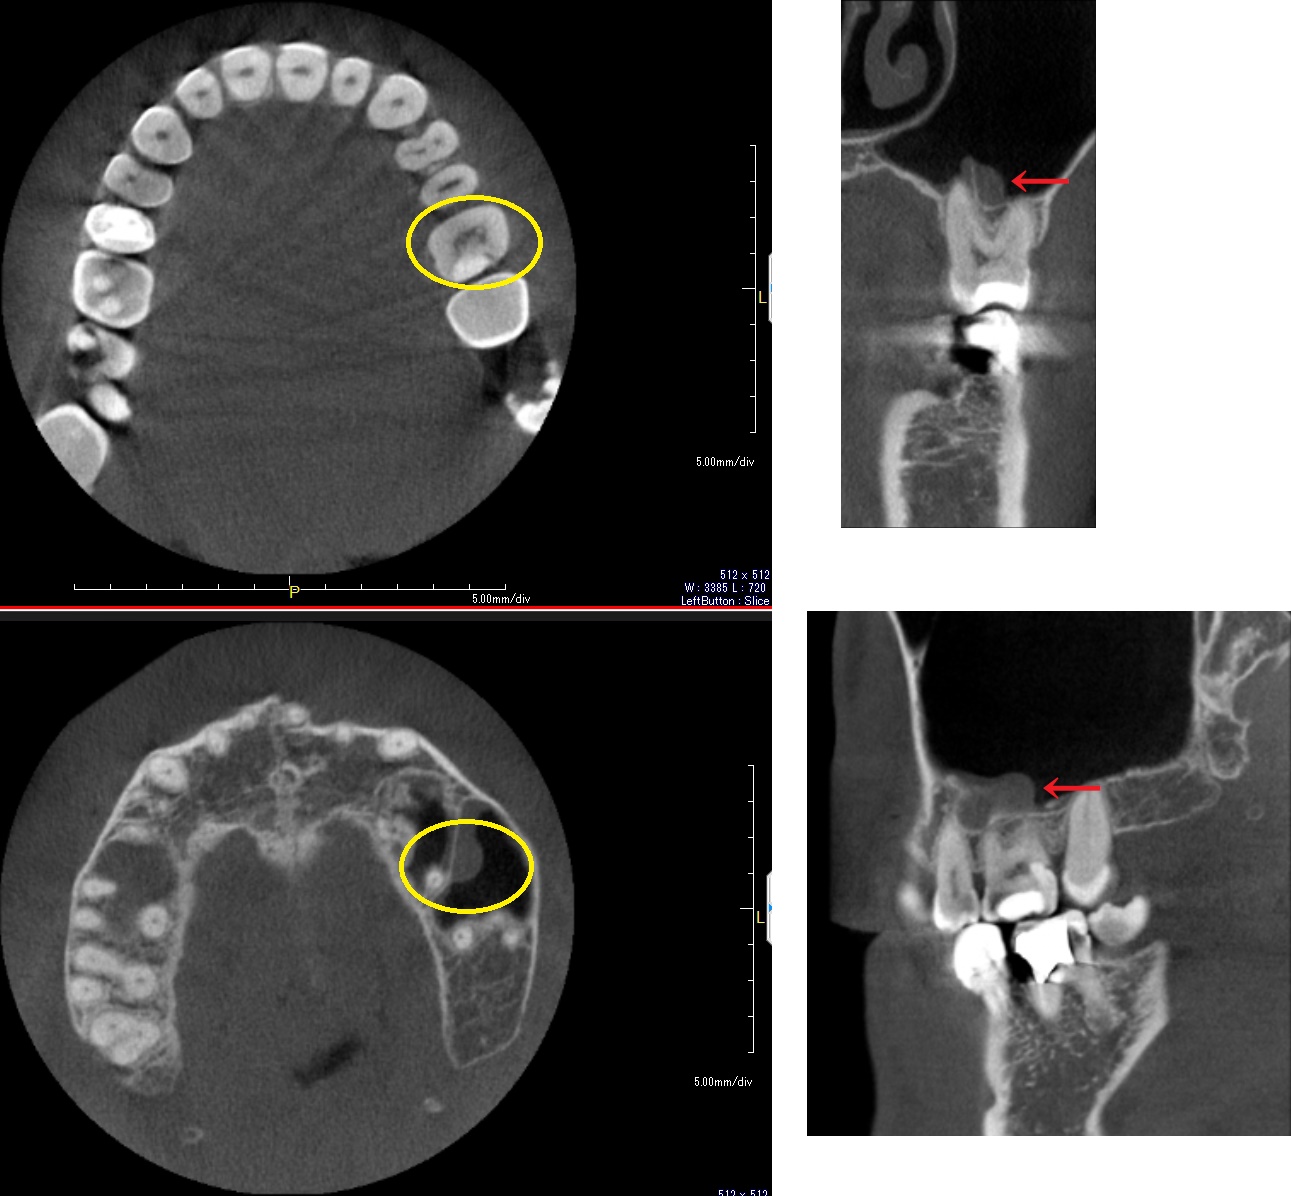

左上6番歯で、添付画像のCTのように、上顎洞内底部で粘膜の肥厚が少し見られます。

CT画像を根尖付近まで進めると、添付画像の左下のように、遠心口蓋側根の根尖からつながるように肥厚が現れます。

上顎洞内のCT画像も添付させてもらいます。

今回対象の左上6番は、上顎洞内のCT画像では向かって右側になります。

向かって左側の大きな肥厚は右上5番歯によるものです。